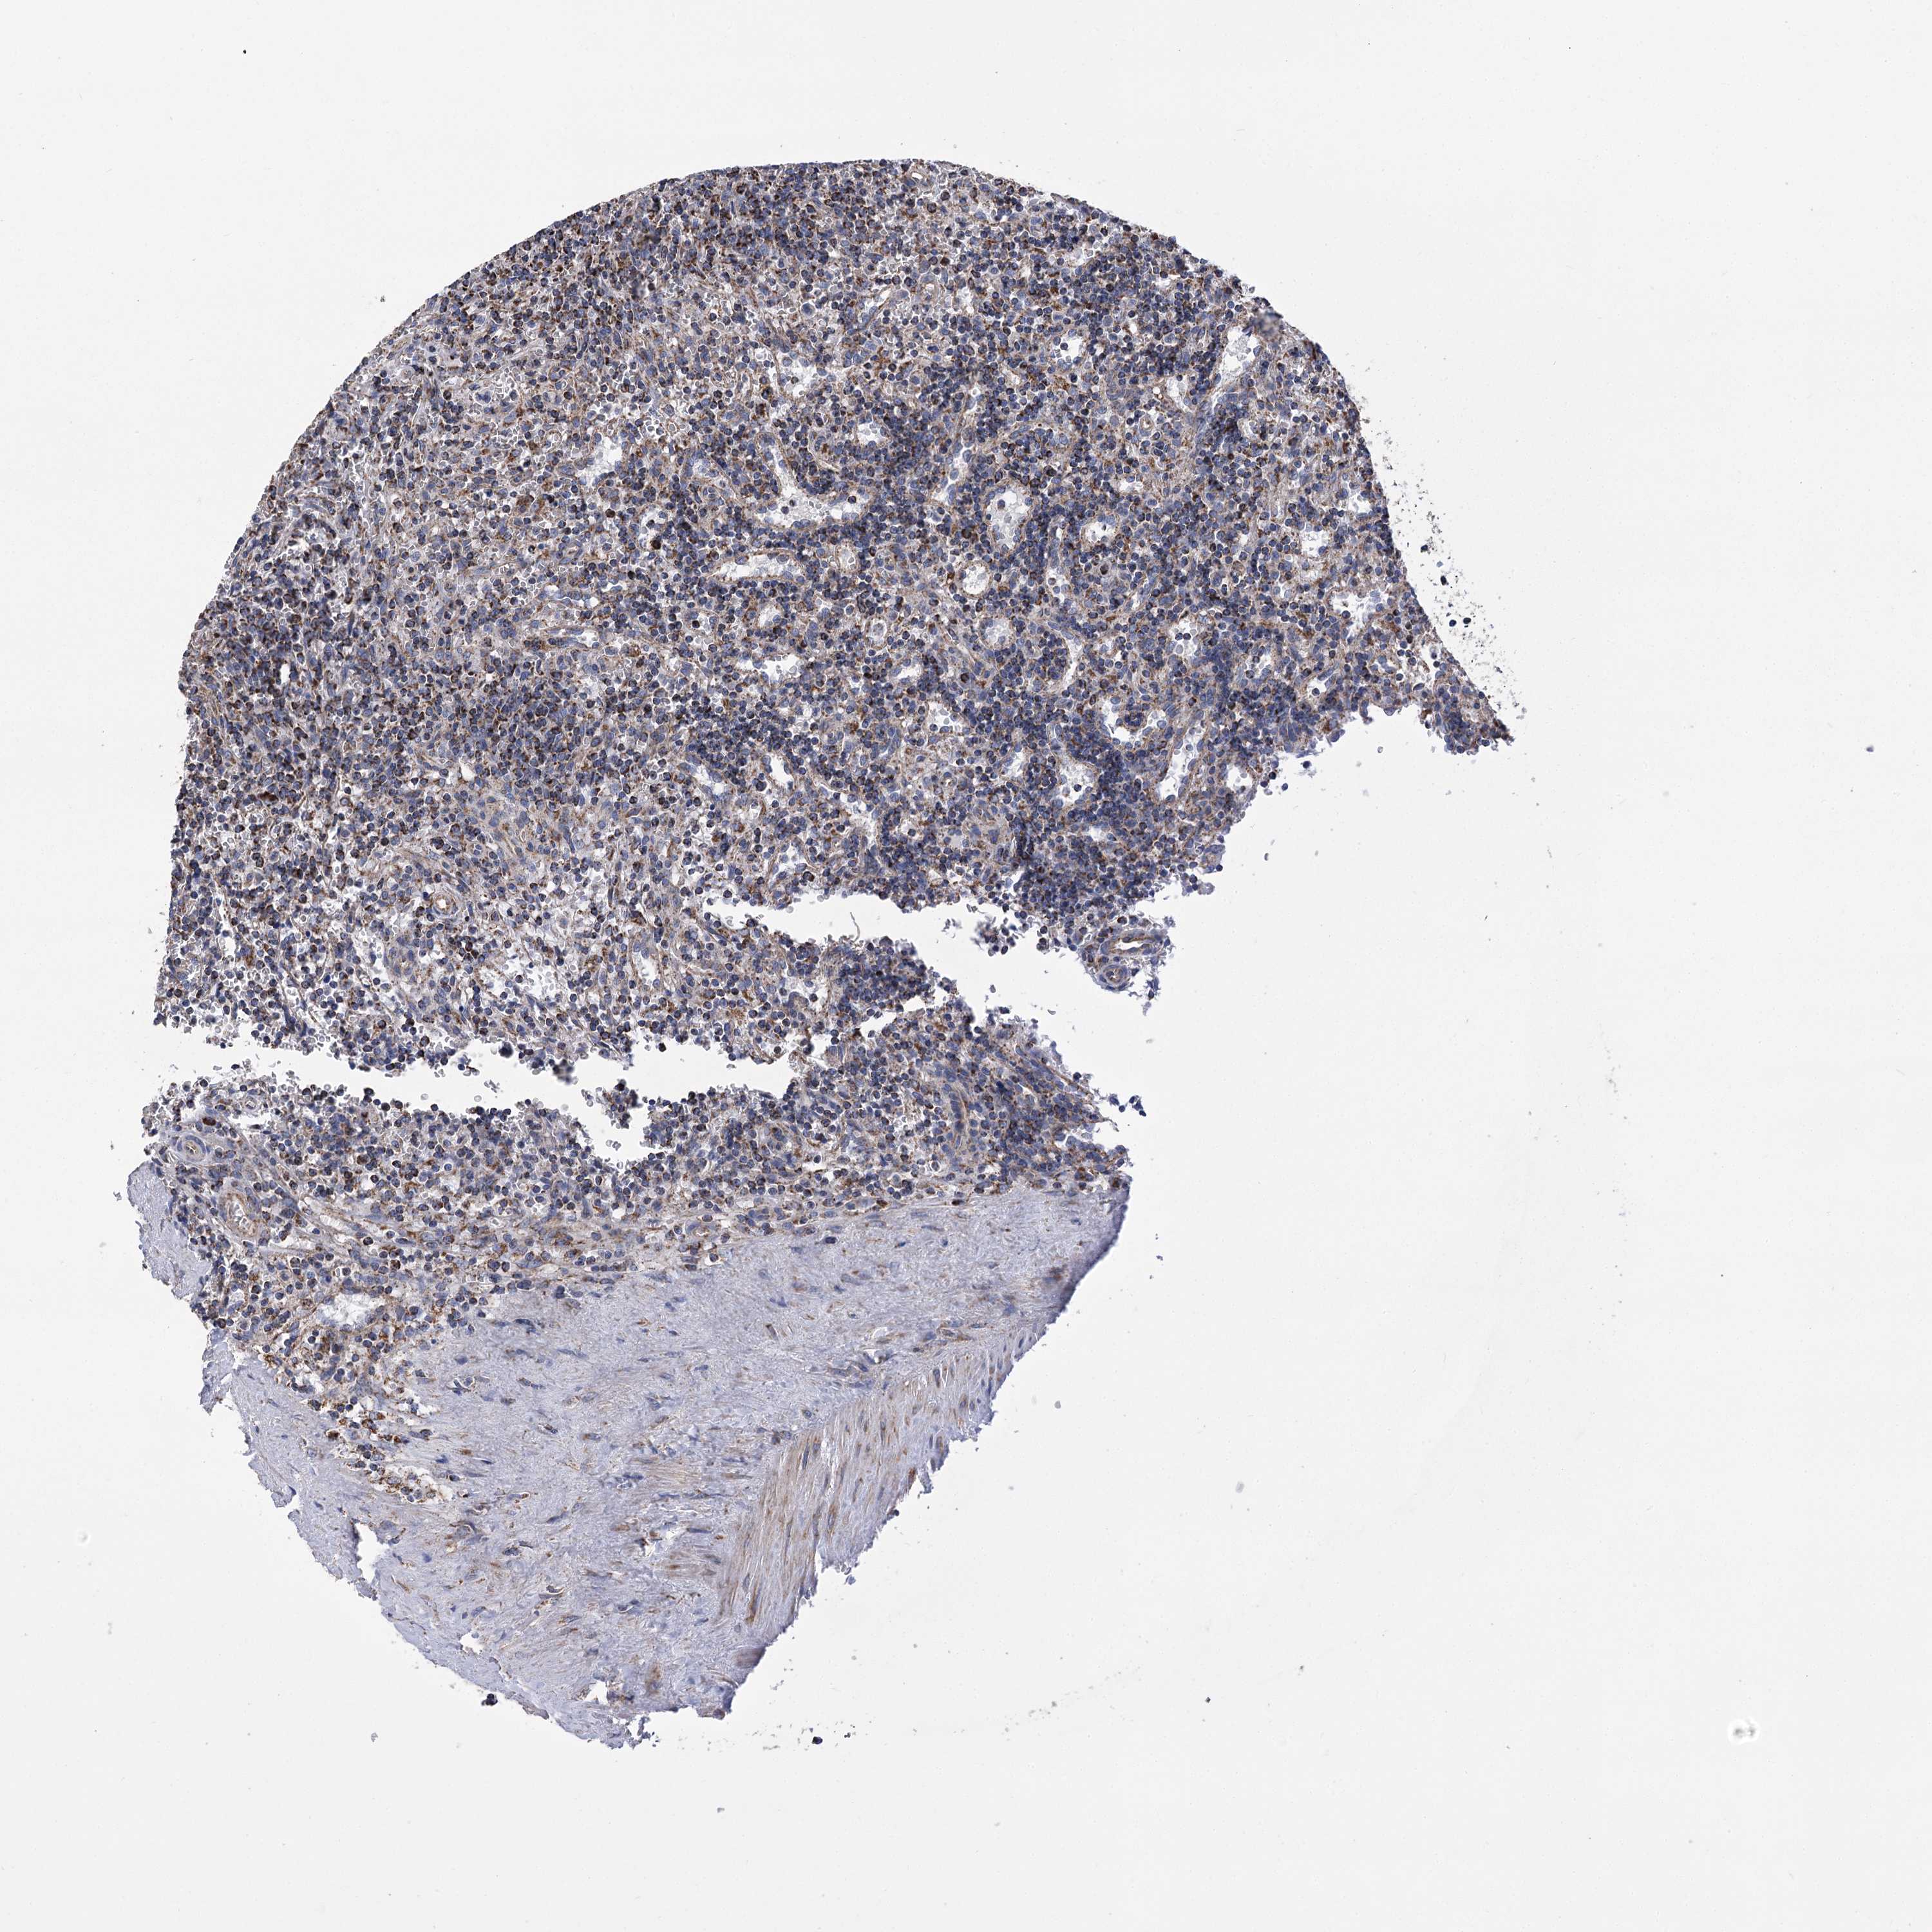

CANCER LYMPHOMA Show tissue menu

LYMPHOMA - Protein expressioni

A mouse-over function shows sample information and annotation data. Click on an image to view it in a full screen mode. Samples can be filtered based on level of antibody staining by selecting one or several of the following categories: high, medium, low and not detected. The assay and annotation is described here.

Each image is clickable and will lead to virtual microscopy that enables deeper exploration of all samples and also displays staining intensity scores, fraction scores and subcellular localization as well as patient and tissue information for each sample.

Antibody HPA038668

Antibody HPA038669

Hodgkin's disease, NOS

Malignant lymphoma, non-Hodgkin's type, High grade

Malignant lymphoma, non-Hodgkin's type, Low grade